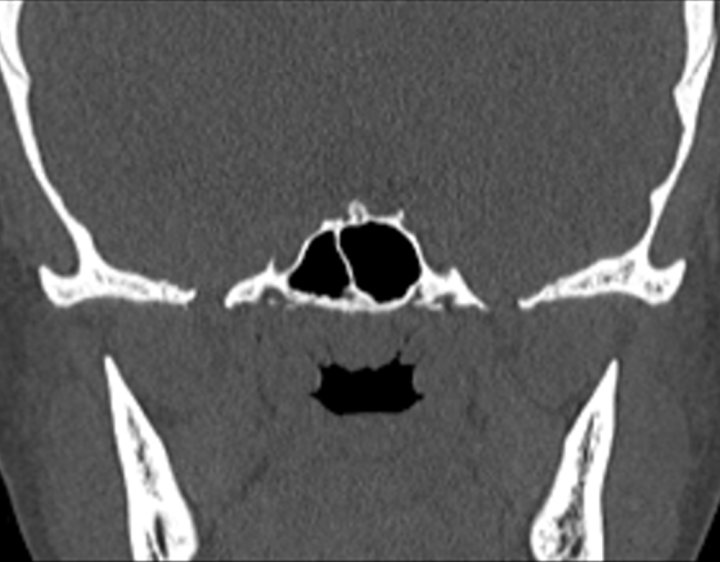

Click any image for labels.